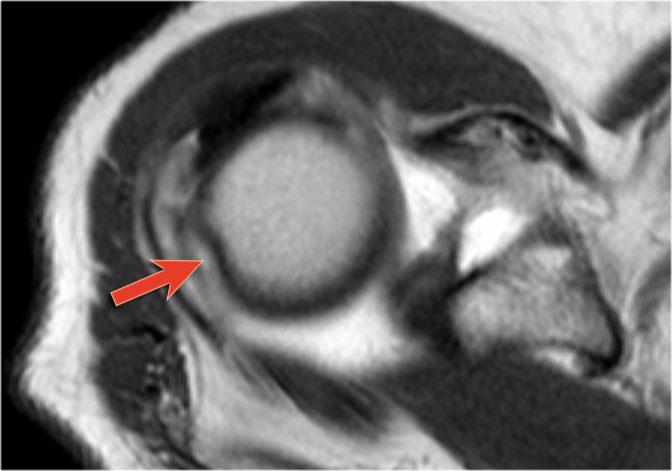

Đây là một bệnh nhân khác có Bankart xương được thấy trên bốn hình ảnh liên tiếp của MRI khớp cản từ ở tư thế ABER.

Lưu ý đường viền bất thường của ổ chảo phía trước và bờ trước bị avulsion (mũi tên)